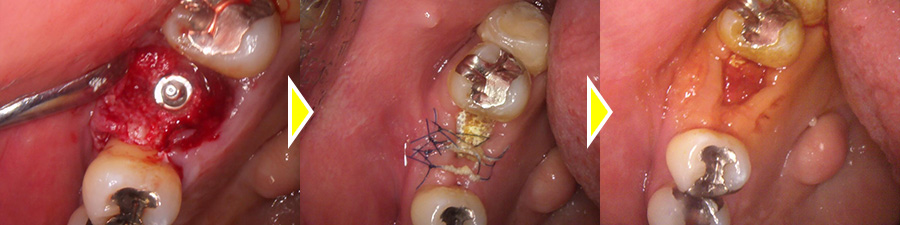

根破折で根の先端に膿がたまっているため抜歯しインプラントで修復した症例

こちらの患者さまは、左上6番目の歯が噛むと痛いとの主訴で来院されました。

レントゲンでの検査の結果、根破折のため根の先端に膿がたまっていることがわかったため、保存不可の為、治療方針の説明を行ったところ、抜歯後インプラントでの治療をご希望されました。

4歯を一度に抜歯後、膿を取り出したところ、範囲が大きく、骨を溶かしてしまっていたため骨に穴があいてしまっていることが実際に肉眼で確認できました。

歯肉は非吸収性のメンブレンで覆いオープンメンブレン法にて処置を行いました。

結果、予後キレイな歯肉ができています。